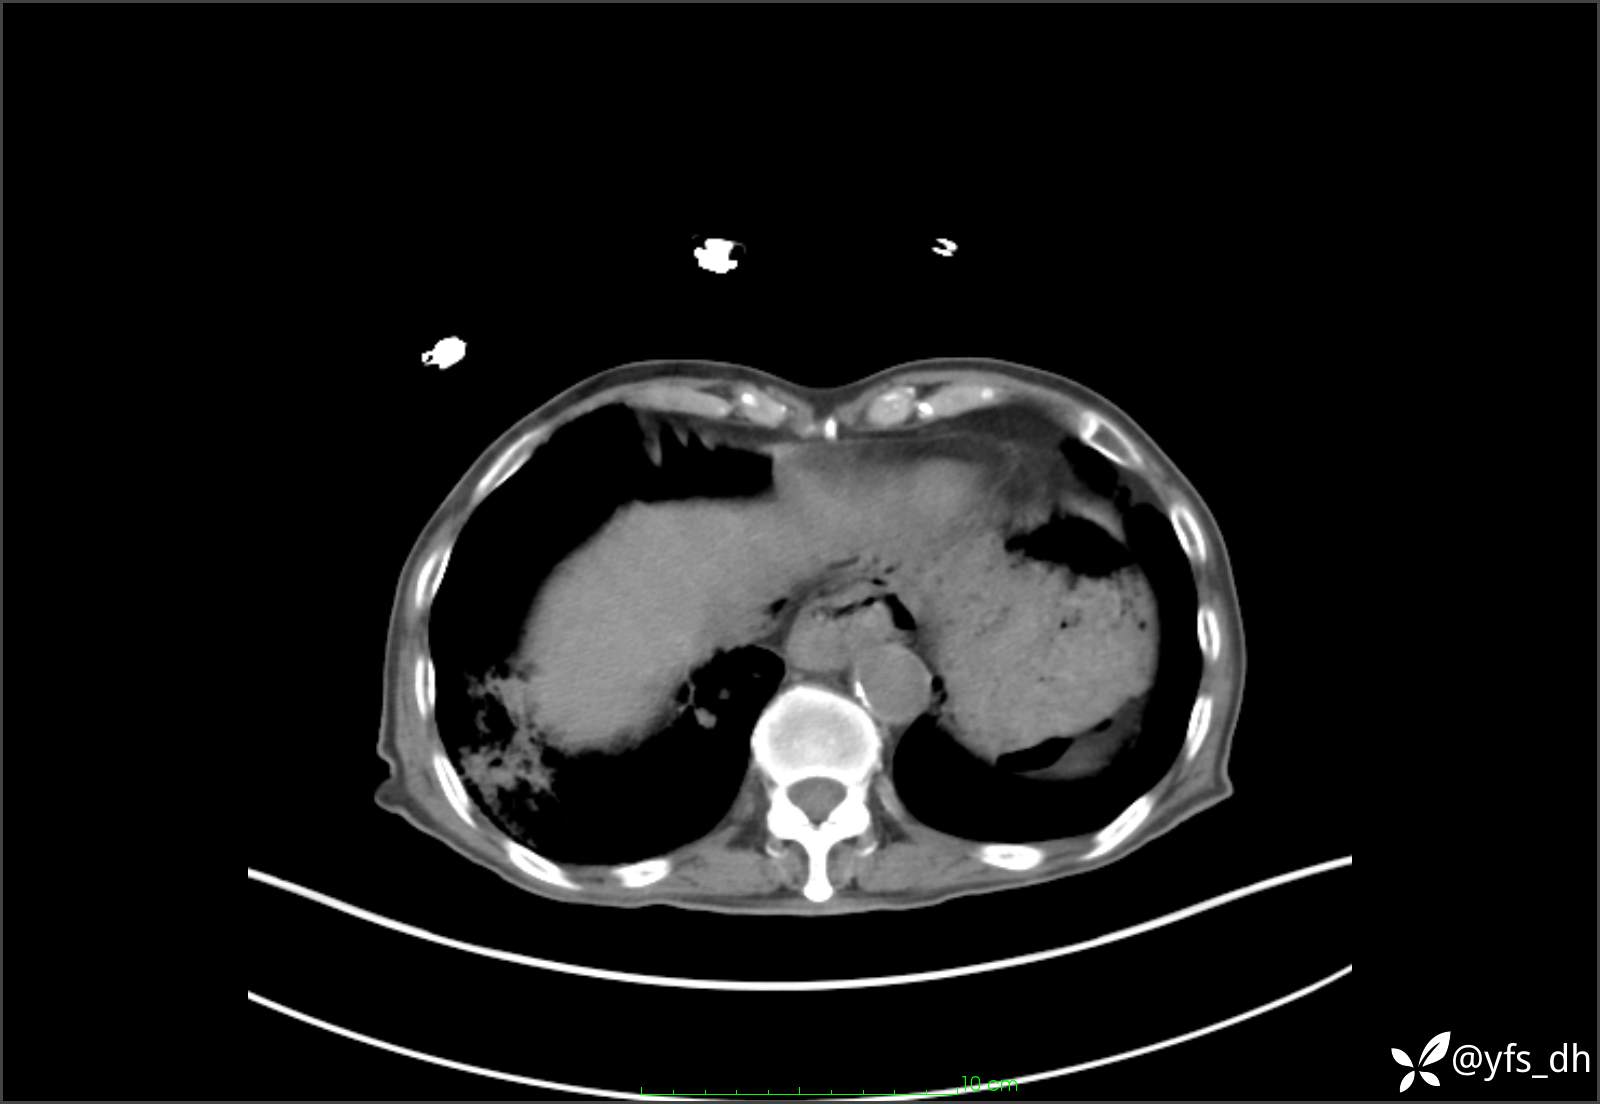

1.简要病史:患者4天前突发上腹部疼痛不适,但可以忍受。3小时前饭后突然加重,不能忍受后就诊。

2.简要手术记录:术中见腹盆腔大量肠液及粪便,乙状结肠中下段见一约3cm的破口。